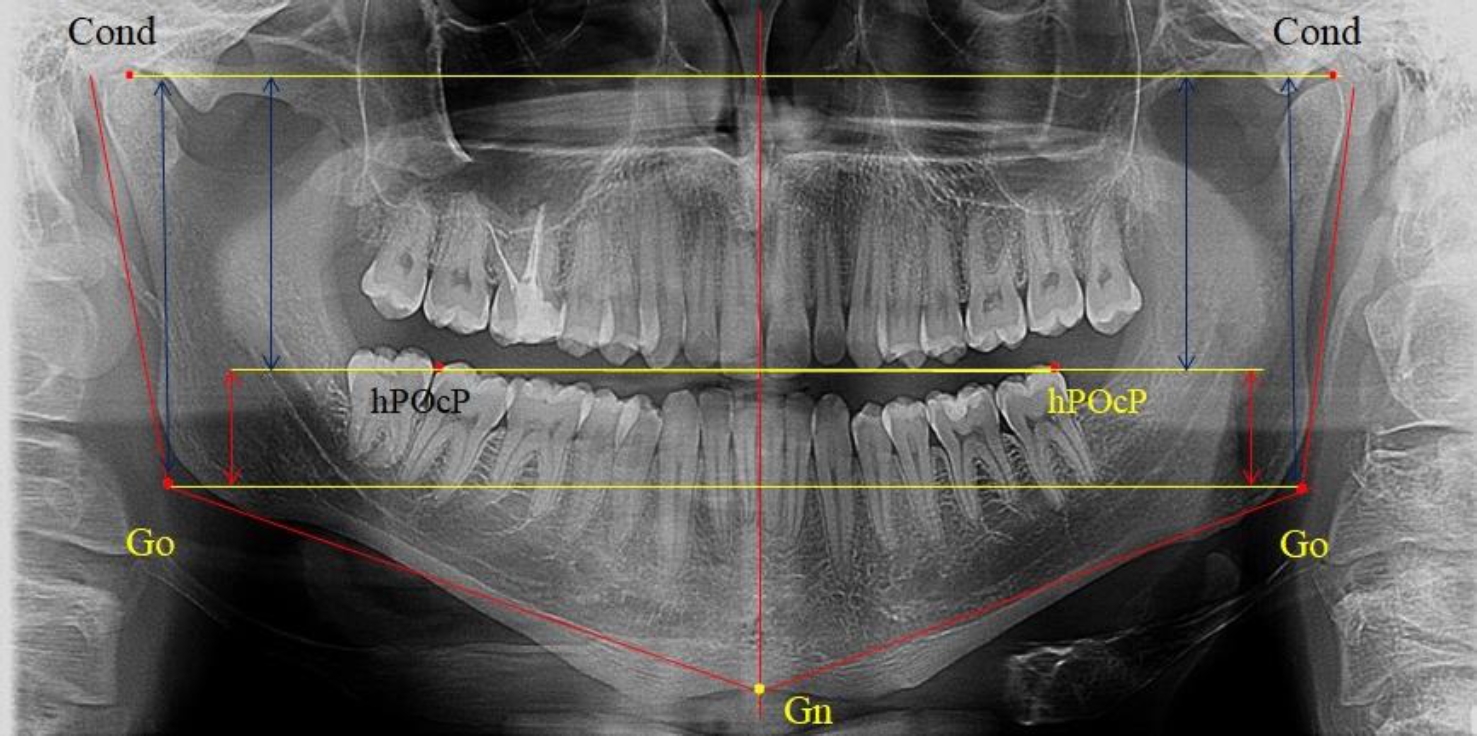

3-я подгруппа была с наименьшим количеством анализируемого материала, и здесь было проанализировано 17 комплектов рентгенограмм [(22,97 ± 4,89) %], на которых средняя величина отношения верхней части ветви к нижней составляла 2,45 ± 0,04, что было достоверно больше показателя, полученного по группе в среднем, а также в 1-й и 2-й подгруппе. Визуально параметры ветви отличались от других подгрупп. Высота ветви составляла (57,83 ± 0,89) мм, что было несколько меньше, чем в других подгруппах. Максимальная высота была 64 мм, а минимальная – 53 мм. Высота верхней части составляла (41,03 ± 0,59) мм, что было близким по значениям, полученным в других подгруппах и свидетельствовало о меньшей вариабельности указанного параметра. В то же время высота нижнего отдела ветви была (16,83 ± 0,36) мм и показатель отличался в меньшую сторону, по сравнению с аналогичным размеров в других подгруппах (рис. 4).

Таким образом, при физиологических вариантах прикуса определены основные вертикальные параметры ветви нижней челюсти и ее составных частей. В среднем высота верхней окклюзионно-суставной части ветви в два раза превышала размеры нижней окклюзионно-гониональной части, что может быть использовано как в клинике ортодонтии, так и челюстно-лицевой хирургии при планировании операций по моделированию ветви нижней челюсти.

Рис. 4. ОПТГ пациента 3-й группы с увеличенным коэффициентом соотношения частей ветви нижней челюсти